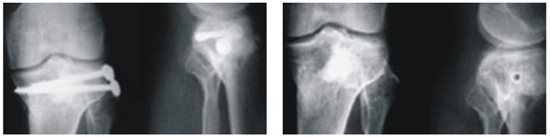

Indications for use:

Product Presentation

|

B-OstIN Granules |

B-OstIN Rod |

B-OstIN Block |